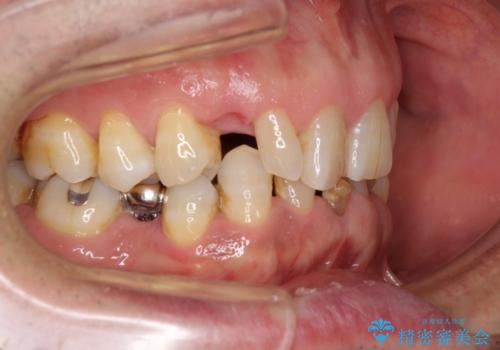

上顎の矮小歯は隙間が多く、歯軸の傾斜も大きかったため、部分矯正により補綴治療前に歯の位置を整えることとしました。

下顎の乳歯は支台歯として機能することは困難と思われたので、事前に抜歯をし、上顎の矯正治療終了のタイミングに合わせて、セラミックブリッジにて補綴治療することとしました。

前歯部はディープバイトという、上顎前歯が下顎前歯に深く覆い被さる咬合であったので、理想的には全顎矯正が必要となりますが、今回は患者希望により前歯部のみの部分矯正で対応しました。そのため下顎犬歯の神経を取り除くことになってしまったのは心残りであります。